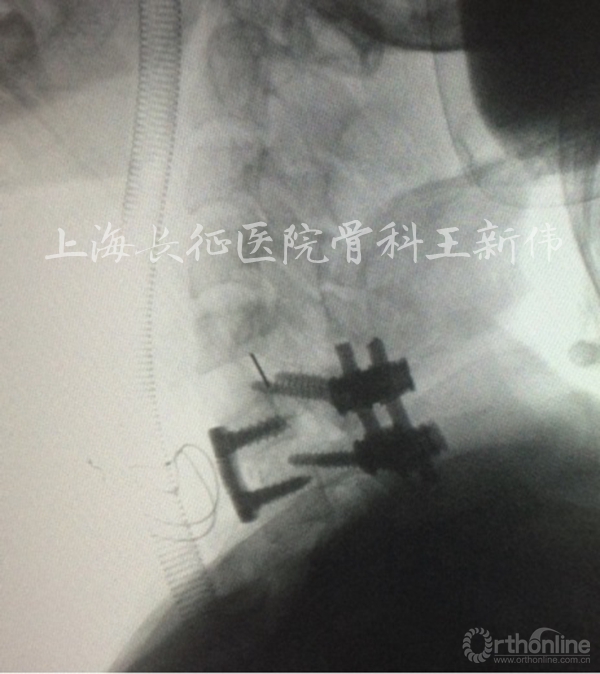

术中磨钻磨开椎板间隙,加压后螺帽固定

术中见内固定位置良好,椎间高度及序列恢复,关节绞锁恢复